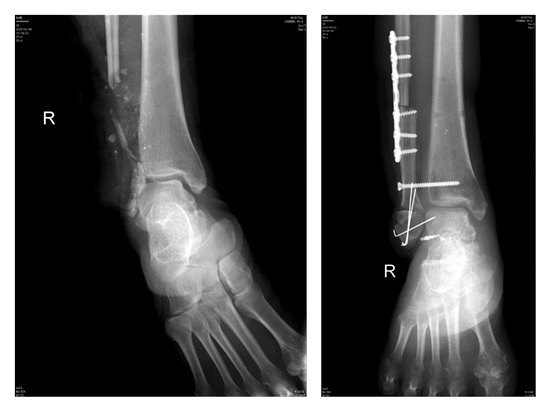

手术前和手术后 医院供图

为了尽量恢复患者患肢负重行走等功能,经与黄女士及其家属充分沟通,待患者右腿满足修复重建条件后,由李敬矿主任主刀,在陈超杰医师的协助下为患者实施左侧游离腓骨头骨皮瓣移植右外踝再造及软组织缺损修复手术。术中,李敬矿主任从患者左侧小腿近端切取长约9cm腓骨头骨瓣并携带大小约19.5cm×6cm皮瓣移植到患者右小腿创面。由于创伤面积大,手术历时10余小时,最终顺利完成。术后,经过严密的观察治疗,患者骨皮瓣存活良好,待腓骨头骨皮瓣血运稳定后,皮瓣周围创面游离植皮修复。目前,患者伤口逐步愈合,保肢成功。

被120送到区中医院时,黄女士严重毁损的右下肢让在场的医护人员都倒吸了一口凉气。右腓骨下段及外踝骨缺损约9cm,大面积血肉缺损达25cm×10cm,皮肉分离,腿骨外露,碎骨茬和着血肉一团模糊,伤口惨不忍睹。如果不及时正确处理,后期存在截肢的可能,情况很不乐观。